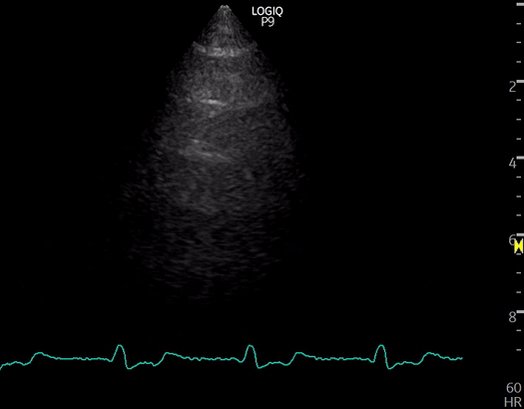

5/ Lungs

Predominantly A-lines, occasional B-lines, but no more than 2 per rib interspace

Representative image👇